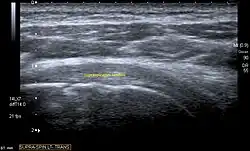

Ultrasound

There are several advantages of ultrasound. It is relatively cheap, does not emit any radiation, is accessible, is capable of visualizing tissue function in real time, and allows the performance of provocative maneuvers in order to replicate the patient’s pain.[28] Those benefits have helped ultrasound become a common initial choice for assessing tendons and soft tissues. Limitations include, for example, the high degree of operator dependence and the inability to define pathologies in bones. One also has to have an extensive anatomical knowledge of the examined region and keep an open mind to normal variations and artifacts created during the scan.[29]

Although musculoskeletal ultrasound training, like medical training in general, is a lifelong process, Kissin et al. suggests that rheumatologists who taught themselves how to manipulate ultrasound can use it just as well as international musculo-skeletal ultrasound experts to diagnose common rheumatic conditions.[30]

After the introduction of high-frequency transducers in the mid-1980s, ultrasound has become a conventional tool for taking accurate and precise images of the shoulder to support diagnosis.[31][32][33][34][35]

Adequate for the examination are high-resolution, high-frequency transducers with a transmission frequency of 5, 7.5, and 10 MHz. To improve the focus on structures close to the skin an additional "water start-up length" is advisable. During the examination the patient is asked to be seated, the affected arm is then adducted and the elbow is bent to 90 degrees. Slow and cautious passive lateral and/or medial rotations have the effect of being able to visualize different sections of the shoulder. In order to also demonstrate those parts which are hidden under the acromion in the neutral position, a maximum medial rotation with hyperextension behind the back is required.[36]

To avoid the different tendon echogenicities caused by different instrument settings, Middleton compared the tendon’s echogenicity with that of the deltoid muscle, which is still lege artis.[37][38]

Usually the echogenicity compared to the deltoid muscle is homogeneous intensified without dorsal echo extinction. Variability with reduced or intensified[39] echo has also been found in healthy tendons. Bilateral comparison is very helpful when distinguishing and setting boundaries between physiological variants and a possible pathological finding. Degenerative changes at the rotator cuff often are found on both sides of the body.[40] Consequently, unilateral differences rather point to a pathological source and bilateral changes rather to a physiological variation.[38]

In addition, a dynamic examination can help to differentiate between an ultrasound artifact and a real pathology.[41]

To accurately evaluate the echogenicity of an ultrasound, one has to take into account the physical laws of reflection, absorption and dispersion. It is at all times important to acknowledge that the structures in the joint of the shoulder are not aligned in the transversal, coronal or sagittal plane, and that therefore during imaging of the shoulder the transducer head has to be held perpendicularly or parallel to the structures of interest. Otherwise the appearing echogenicity may not be evaluated.[42]